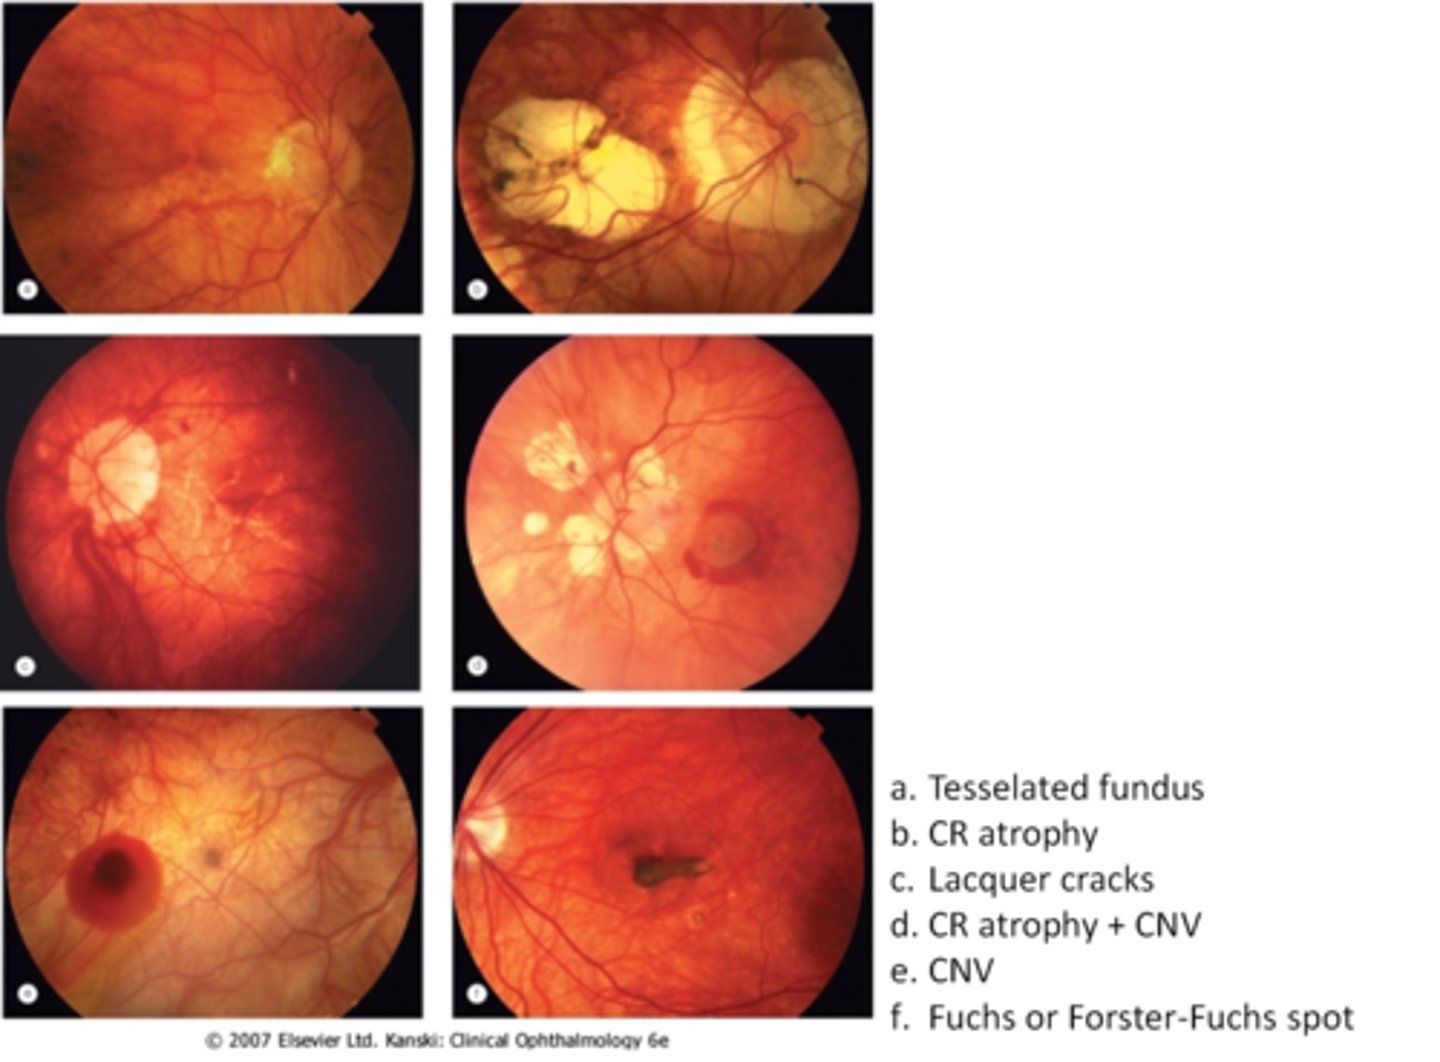

tesselated or tigroid fundus = visibility of choroidal vasculature (A)

What are some common findings in degenerative myopia?

lacquer cracks (C)

CNV (E)

chorioretinal atrophy (B)

What findings of degenerative myopia are seen here?

PPA

crescent

lacquer cracks

How do lacquer cracks appear on fundoscopy?

jagged, irregular yellow lines showing sclera in the posterior pole